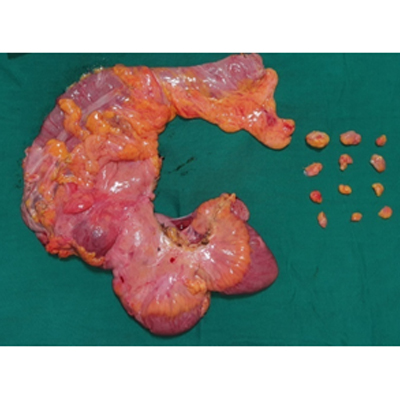

SURGERY FOR COLON CANCER

LAPAROSCOPIC SURGERY FOR BILIARY CYST